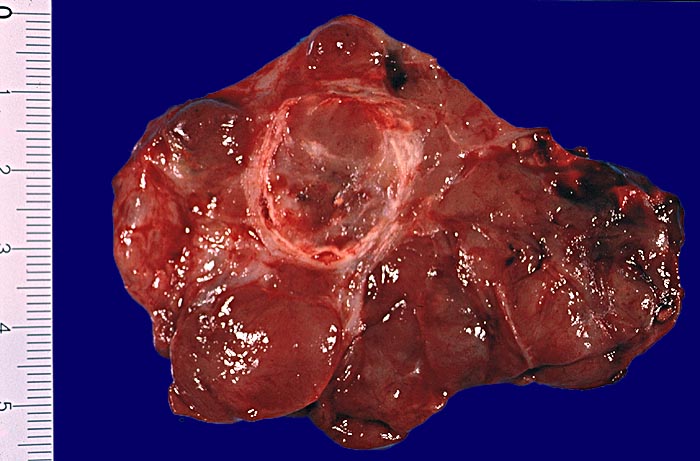

Makroskopie

Befund

Pathologischer Befund

Normalbefund